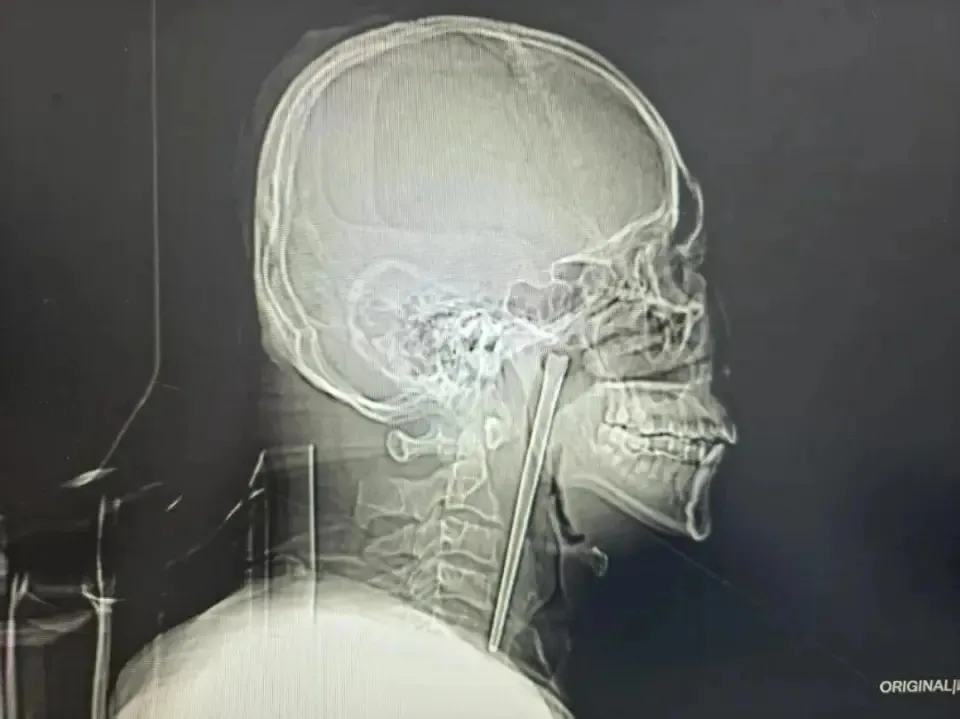

医生检查发现,王先生右侧咽后壁上方软腭后侧有一根金属筷子嵌入其中,外露大约3cm。

考虑到王先生害怕手术,医生为他定制了无需在颈部开刀的方案,成功透过微创手术将这根12cm的筷子完整取出。